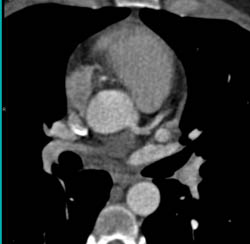

Dilated Origin of RCA and Left Main Coronary Artery